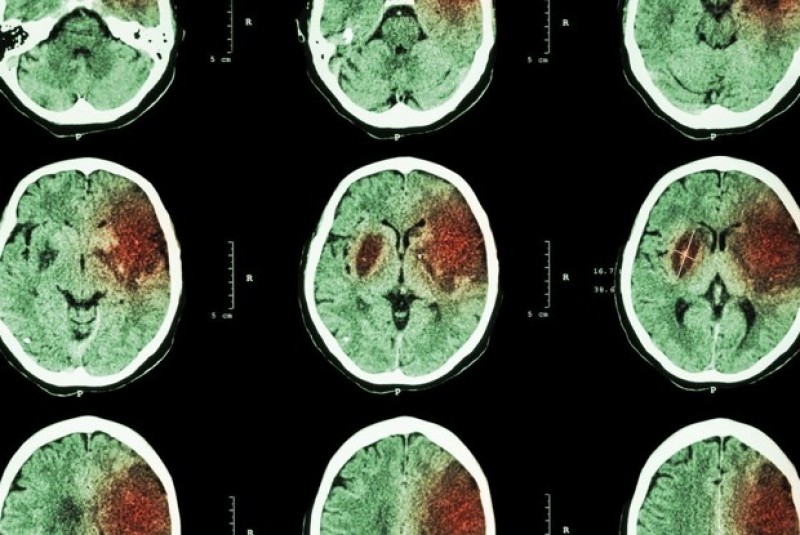

| Hình ảnh các cục máu đông có khả năng gây tắc mạch máu não và gây ra đột quỵ. (Nguồn: CityLab) |